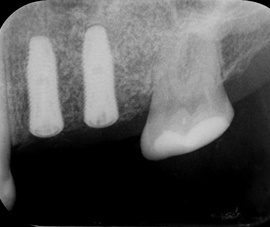

Pacjentka po ekstrakcji kilku zębów, z implantacją natychmiastową, odroczoną. Zdjęcie pantomograficzne wykonano pięć lat po implantacji. Widoczna stabilna sytuacja kostna i dziąsłowa.